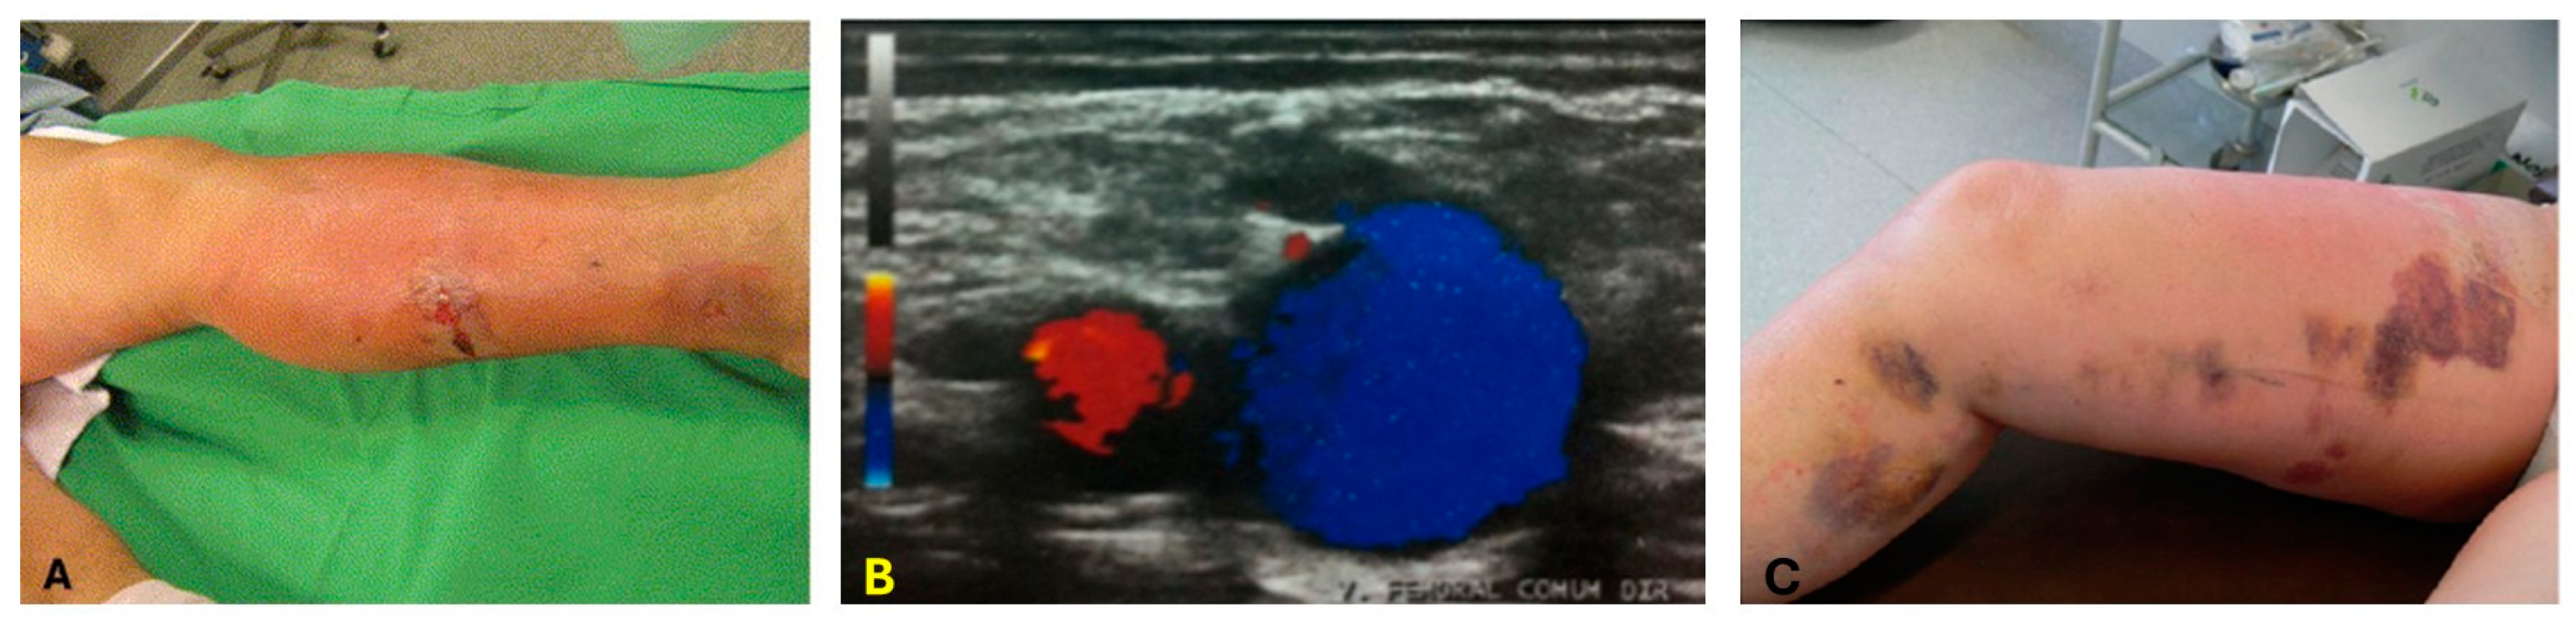

A lack of non-invasive thermometry features leads to an uncontrolled dose, which induces overheating in the surrounding tissue. In the case of EVLA, for example, the overheating of the perivenous tissues causes skin burns (Figure 2A) and thrombosis (Figure 2B). High peak temperatures within the vein perforates the vein wall, inducing more perivenous damage, causing more pain and ecchymosis [37,38,39] (Figure 2C). In some cases, a lack of control over the thermal dose deposition may lead to the delivery of an insufficient thermal dose inducing the recurrence of varicose veins. In some clinical laser ablation procedures, such as Twin-to-Twin Transfusion syndrome, the low-contrast images due to the scattering of light in the endoscope [40] and the lack of quantitative information in the images limits its ability to confirm the extent of ablation. The effectiveness of laser ablation procedures depends on the accurate placement of the laser applicator within the diseased tissue and monitoring the real-time temperature variations during the ablation procedure.

Figure 2.

Limitations of EVLA without proper thermometry. These limitations include (A) skin burns. The image was adapted from [41]; (B) endovenous heat-induced thrombosis (EHIT). The image describes the thrombus flow within the vein. The flow of thrombus moving toward the transducer is color-coded in red, and blue indicates the flow away from the transducer. The image was adopted from [42]; (C) ecchymosis. The image was adapted from [43].